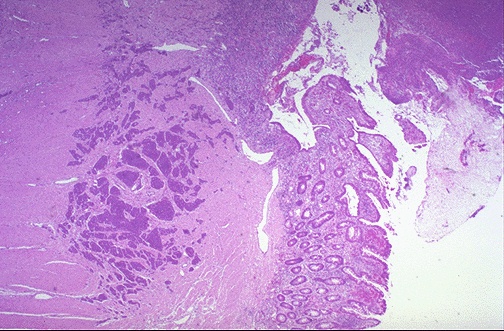

| At low magnification, the small blue nests of tumor cells in this carcinoid tumor are grouped together beneath the mucosa, but are not encapsulated and appear to "infiltrate" in the muscularis, though this is not strictly invasion. It is rare for a carcinoid <1 cm to behave in a malignant fashion, while the majority >2 cm are malignant. Most carcinoids are <1 cm. |